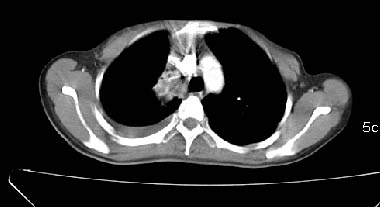

以下是引用zjzjr在2007-3-15 13:31:00的发言:[br]支持楼主诊断.右侧中央型肺癌伴右上叶节段性肺不张、胸腔积液、纵隔淋巴结转移。

以下是引用zyx168在2007-3-15 17:05:00的发言:[br]右侧中央型肺癌伴右上叶节段性肺不张、胸腔积液、纵隔淋巴结转移。